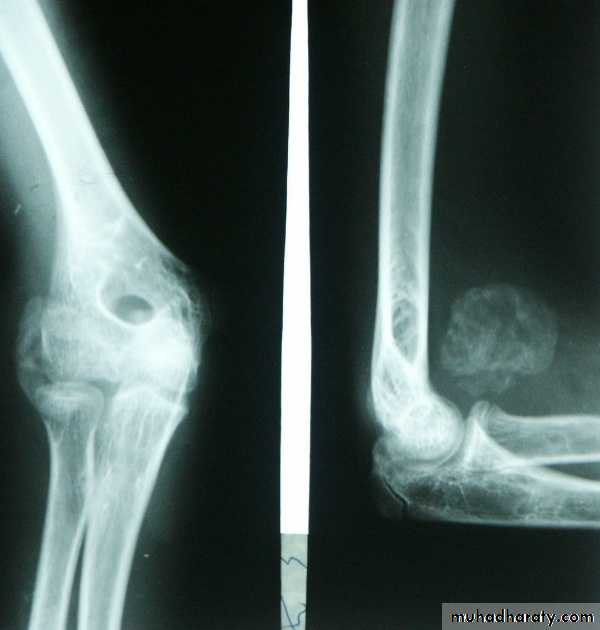

PRINCIPLE of fracturesFracture definition: It is a break in the structural continuity of bone .

3.abnormal weakening of the bone (pathological fracture).

In cancellous bone trauma produce comminuted crush fracture.

Around joint pulling ligament and tendon produce avulsion fracture.How fracture are displaced:

X-ray.